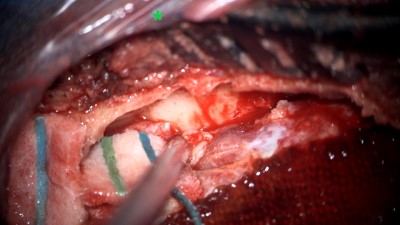

Intraoperative photo demonstrating the operative approach. A right temporal craniotomy has been made and the covering of the brain, the dura mater, is being dissected off of the base of the skull. Orientation: this is the right side of the head; the ear is just off the top of the frame (green star(*)), the nose is to the left, the back of the head the right, and the top of the head is toward the bottom.

Intraoperative video demonstrating the dissection of the encephalocele. Note the band of tissue extending from the skull base defect on the top of the image through the dural defect toward the bottom. This is the encephalocele.